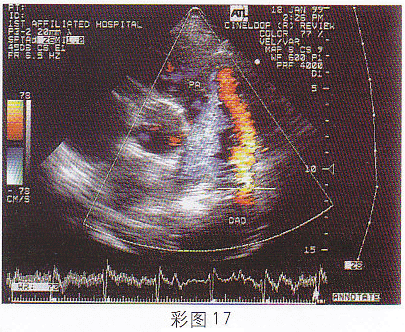

3.該病例最有可能診斷為(彩圖17)

正確答案:B 解題思路:降主動脈與左肺動脈間見分流信號。